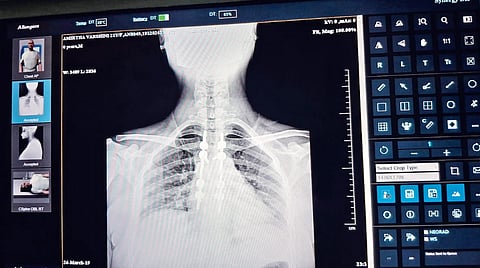

CHENNAI: A shortage of X-ray films has the Kilpauk Medical College (KMC) Hospital asking patients to take photos of x-ray images on their mobile phones and show them to doctors.

For a hospital that has a daily patient footfall in thousands, this raises serious concerns, as poor image quality could lead to misinterpretation and misdiagnosis, putting patient lives at risk.

Dr S Perumal Pillai, president of the Government Doctors' Association, told this correspondent that x-ray sheet shortage is a statewide crisis, and most government hospitals are currently grappling with the problem. Perumal warned that if doctors are forced to diagnose patients by looking at images on their mobile phones, it could lead to misdiagnosis and put lives in danger. He noted that physical X-ray sheets remain the reliable way to accurately read and diagnose a patient's condition.

The Indian Council of Medical Research and the National Medical Commission provide specific frameworks for doctors using digital images for diagnosis. Under the Telemedicine Practice Guidelines, diagnosing a patient using a smartphone image of an X-ray is legally permissible, but it carries significant professional responsibilities and technical risks.